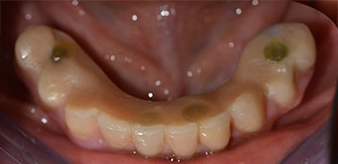

The 64-year-old patient presented with residual dentition of teeth 38, 33 and 43 and a clasp denture in the mandible (Fig. 1 and 2).

A three-dimensional cone beam computed tomography scan (CBCT, Planmeca) was performed to aid planning and minimize risks. This revealed that the quality and quantity of the available bone were sufficient for the surgery and immediate restoration using the Fast & Fixed method. Following the protocol for this concept, the implants are inserted at 35, 32, 42 and 45. Angling the distal implants by up to 45° shifts the emergence profile to posterior and generates a larger support polygon (Fig. 3).